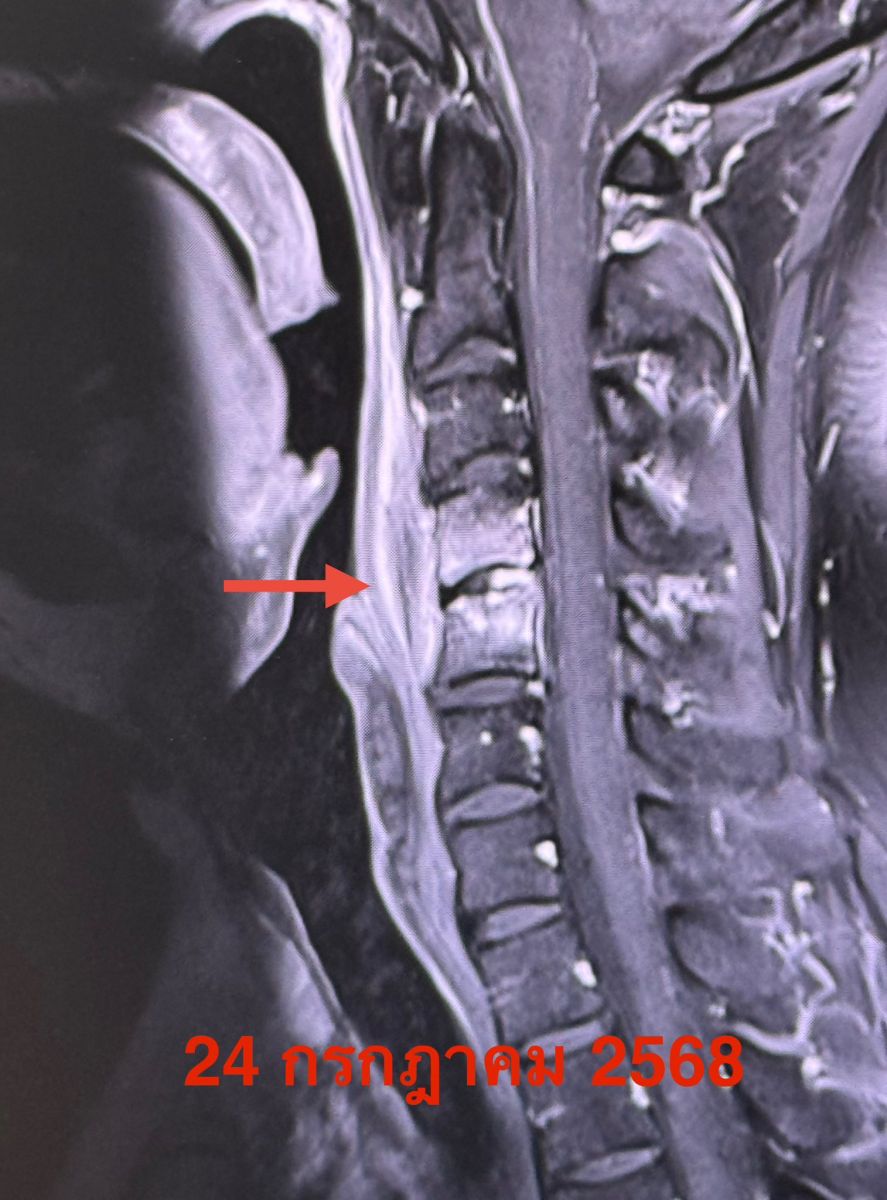

วันที่ 5 กค. สงสัยติดเชื้อลามออกมาที่เนื้อเยื่ออ่อนหน้าเยื่อหุ้มไขสันหลัง (Anterior epidural infection) บริเวณกระดูกคอข้อที่ 4 และ 5

ผู้ป่วยแพ้ยาเพนิซิลลิน ได้ยาปฏิชีวนะ clindamycin ทางเส้นเลือดเป็นเวลา 1 เดือน ทำ MRI ซ้ำ วันที่ 24 กค.พบการอักเสบที่เนื้อเยื่ออ่อนหน้าเยื่อหุ้มไขสันหลัง (Anterior epidural infection) บริเวณกระดูกคอข้อที่ 4 และ 5 ลดลง ได้ยาปฏิชีวนะชนิดกิน levofloxacin ต่ออีก 3 เดือน คนไข้ดีขึ้นมาก ไม่มีไข้ ไม่ปวดต้นคอ ไม่มีกล้ามเนื้ออ่อนแรง เดินได้ปกติ